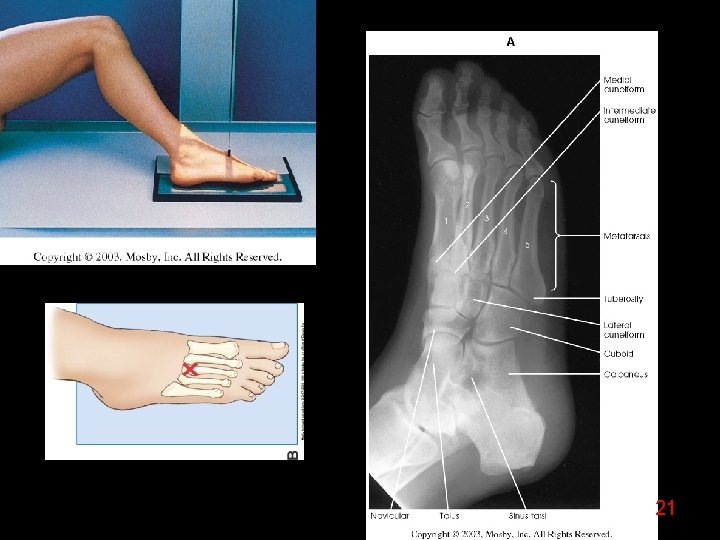

20

21